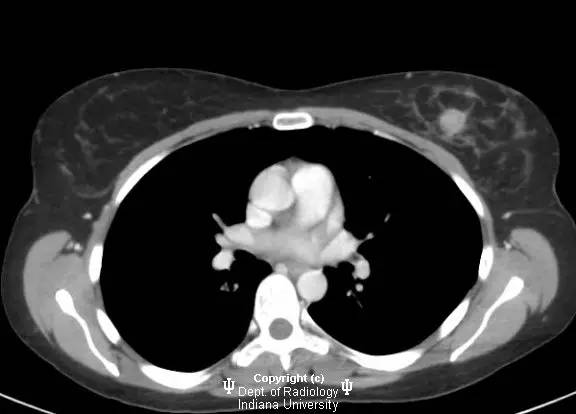

【影像学表现】

乳腺钼靶左乳腺内上象限见3.1cm卵圆形等密度肿块,部分界限清晰。超声见一2.5 x 2.1 x 1.9 cm混合回声肿块,宽大于高,边界清晰,后部回声增强。

浸润性导管癌

Invasive ductalcarcinoma

浸润性导管癌为乳腺癌的最常见类型(80%),有人认为由导管原位癌进展而来,病变可沿着真皮淋巴管播撒而导致皮肤增厚和乳头内陷。肿瘤多无症状,筛查时发现。女性多于中年好发。浸润性导管癌也是男性乳腺癌的最常见类型。淋巴结累及时提示预后不良。诊断多经超声引导下或立体定位活检。局限性病变治疗主要为手术,也可行放疗,化疗和激素治疗。